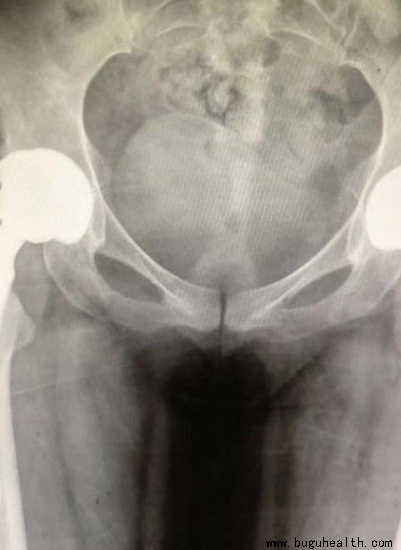

布骨医学科普:中青年早期股骨头坏死的保髋治疗方法!

BuGuRMC布骨康复医疗中心 ,2023-03-01

股骨头坏死(osteonecrosis of the femoral head,ONFH)是关节外科常见且难治的疾病之一,是由多种因素引起股骨头血运异常,进而引起ONFH及塌陷,最终导致髋关节功能严重障碍的疾病。美国每年ONFH新发病例在2万~3万人,主要以20~50岁中青年为主。一项流行病学调查显.....